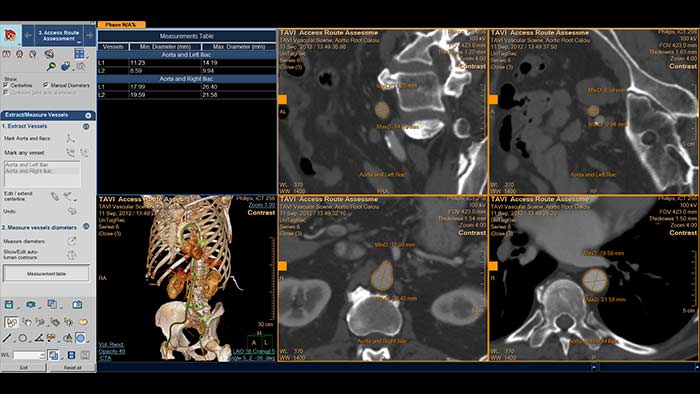

Evaluación automatizada de la ruta de acceso Intellispace Cardiovascular